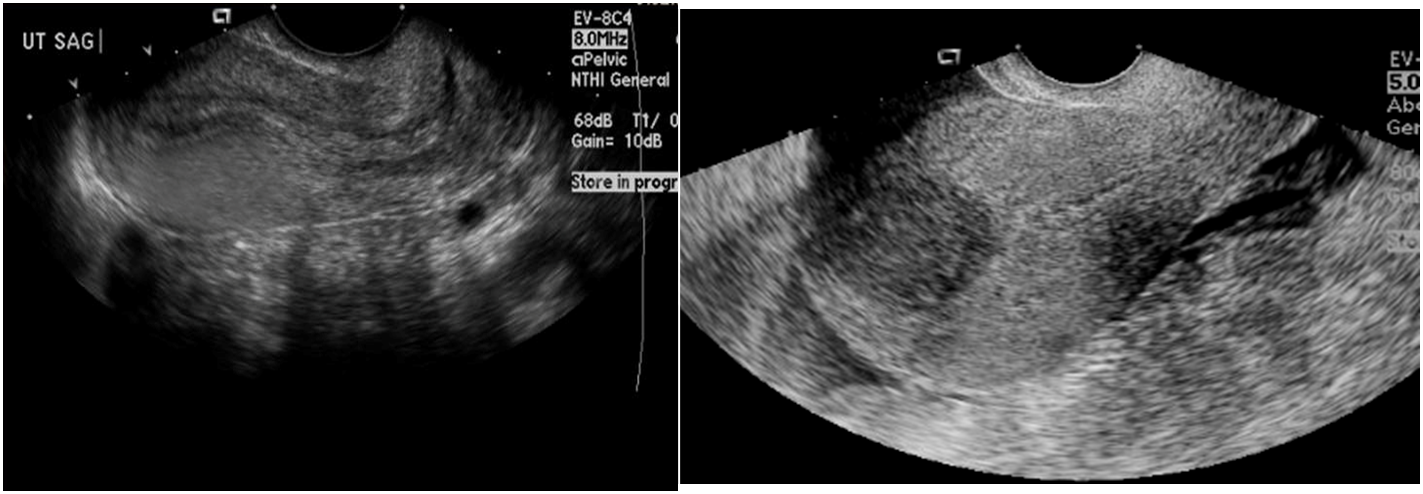

Ultrasound pelvis (transvaginal, transabdominal)

Most appropriate initial test for all patients with a suspected uterine leiomyoma

Supportive findings

- Well-circumscribed hypoechoic solid mass

- Calcifications and/or cystic areas due to degeneration

Hypoechoic lesion in uterus is a typical appearance of a uterine leiomyoma